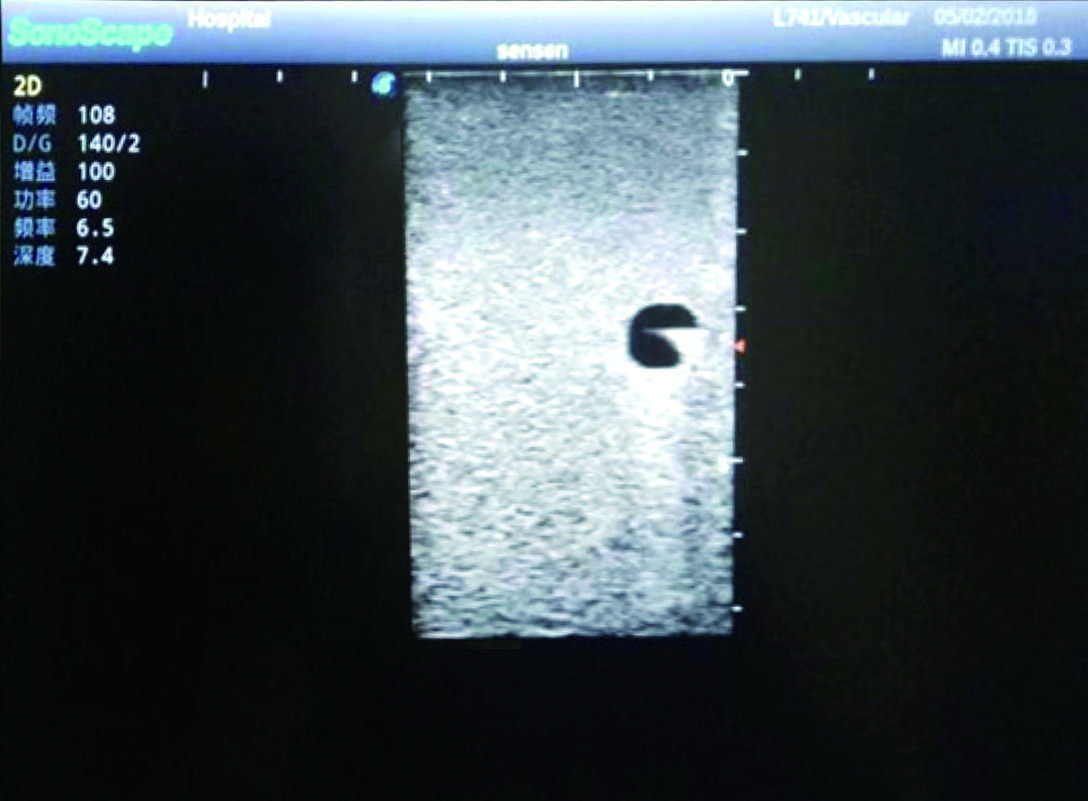

Model TYE1510.1

Outline

It is a model covering up from lobulus auriculae plane to the umbilical plane, and it has anatomical structures like clavicle, rib, sternocleidomastoid, jugular vein and basilic vein.

1)   Made of high molecular polymer ultrasound material, close to the real skin

2)   It can be used by real ultrasound machines

3)   Clear and real images of the tissues and organs (basilic vein and superior vena cava)